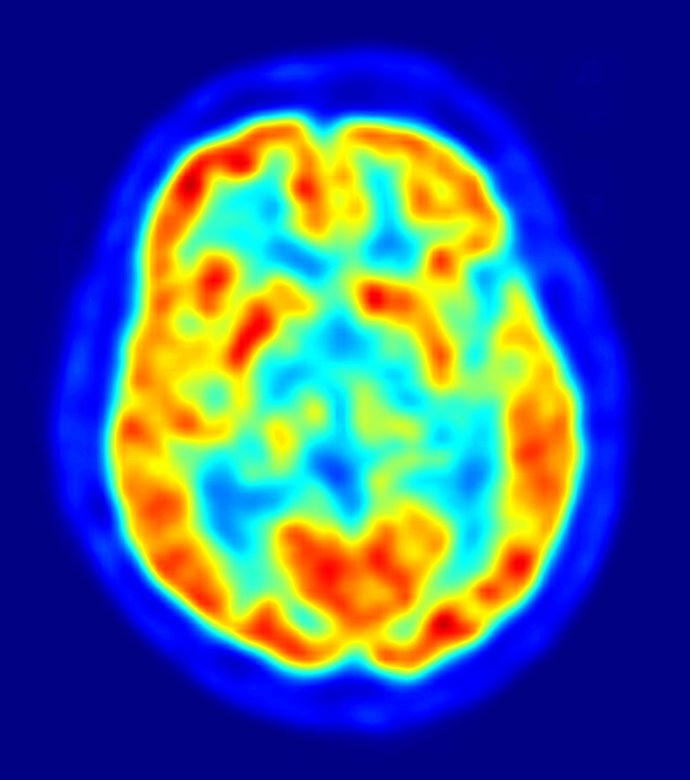

La mayoría de los genes asociados con enfermedades psiquiátricas se expresan antes del nacimiento en el cerebro humano en desarrollo, según un estudio publicado en 'Nature', encabezado por investigadores de la Universidad de Yale, en Estados Unidos. Además, los científicos han identificado cientos de diferencias genéticas entre hombres y mujeres, durante el proceso por el que sus cerebros toman forma dentro del útero.

La creación de cientos de miles de millones de células cerebrales, y el incalculable número de conexiones entre ellas, es una tarea tan compleja que el 86 por ciento de los 17.000 genes humanos estudiados participan en el proceso. El estudio evaluó no sólo qué genes están implicados en el desarrollo, sino dónde y cuándo se activan.

El estudio ha identificado los genes expresados ??en el cerebro humano -y cuándo y en qué parte del cerebro que se expresan- en 1.340 muestras de tejido de 57 sujetos de edades comprendidas entre los 40 días después de la concepción hasta los 82 años. El análisis proporciona un mapa sin precedentes de la actividad genética del cerebro en diferentes etapas de desarrollo.